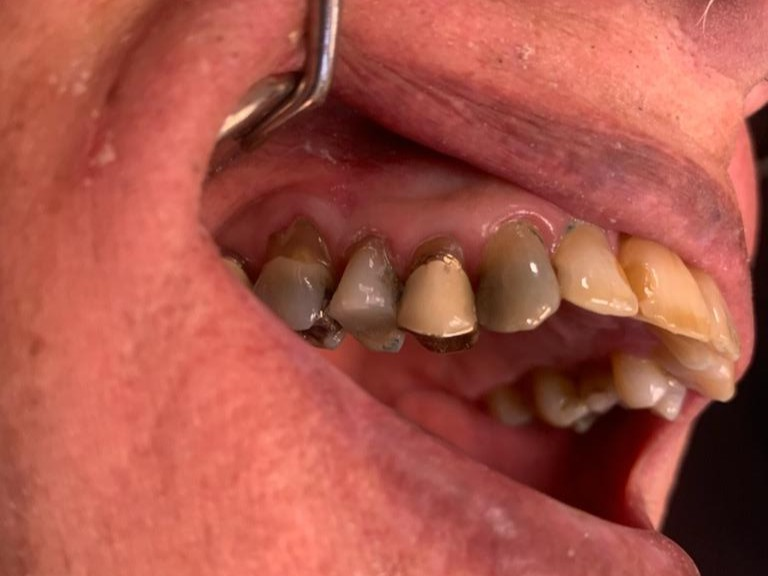

3

Anterior broken tooth. Double DentXpinTM repair.